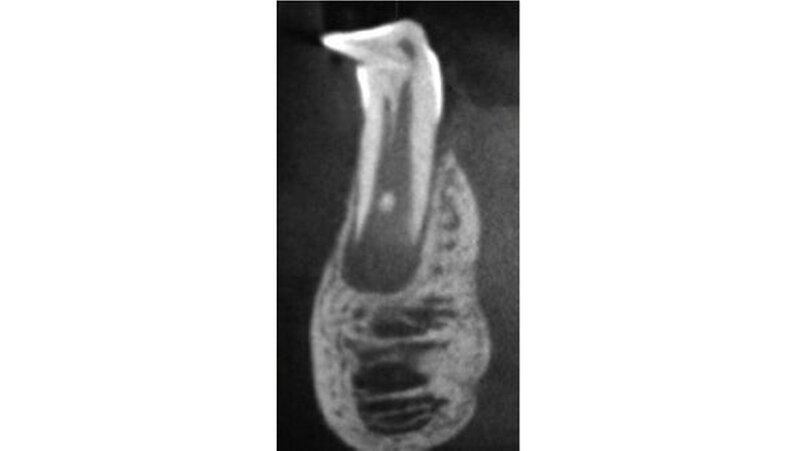

Alles, was bereits vollständig mineralisiert ist, ist nicht oder kaum betroffen. Bei einer axialen Stauchung des bleibenden Zahnkeims durch die Milchzahnwurzel kommt es zur sogenannten kalizotraumatischen Linie, bei einer erheblichen nicht-axialen Stauchung zur Verlagerung der bereits mineralisierten Zahnhartsubstanz. Die nach dem Unfall weiter fortschreitende Mineralisation des Zahns folgt nicht etwa der neuen Lage des Zahns sondern wählt den Weg, der ihr genetisch vorgegeben wurde - unabhängig von der Lage und Position des bereits mineralisierten Anteils.

Die Folge ist ein mehr oder weniger ausgeprägter scharfer Knick im Zahn. Davon abzugrenzen ist die ebenfalls unfallbedingte vestibuläre Wurzelkrümmung (Vestibular root angulation), die eine Biegung der Zahns/der Wurzel und keinen Knick aufweist. Diese entsteht häufiger nach Milchzahnavulsion, wo der Zahnkeim langsam eine andere Durchbruchsrichtung einschlägt. Ursache ist unter anderem eine lokale Fibrosierung im Bereich der Milchzahnalveole.

Dilazeration (Abb. 1 bis 7) kann zur Durchbruchsstörung des betroffen Zahns führen. Fast immer sind auch Farb- und Formanomalien des Schmelzes zu beobachten. Die Erhaltungsmöglichkeit solcher Zähne hängt primär von der Schwere und Lokalisation der Missbildung, aber auch vom Grad der Farb- und Strukturanomalie ab. Malformationen im mittleren oder apikalen Wurzeldrittel sind ohne Einfluss auf den dentogingivalen Verschluss und haben in der Regel wenig Einfluss auf den Zahnerhalt - die Pulpa bleibt hier in den meisten Fällen vital.

Bei ausgeprägten Missbildungen wie im beschriebenen Fall im Bereich des Zahnhalses ist der konservierende und endodontologische Zahnerhalt - obwohl angestrebt - oft nicht mehr möglich. Dies muss jedoch im Einzelfall diskutiert und entschieden werden.